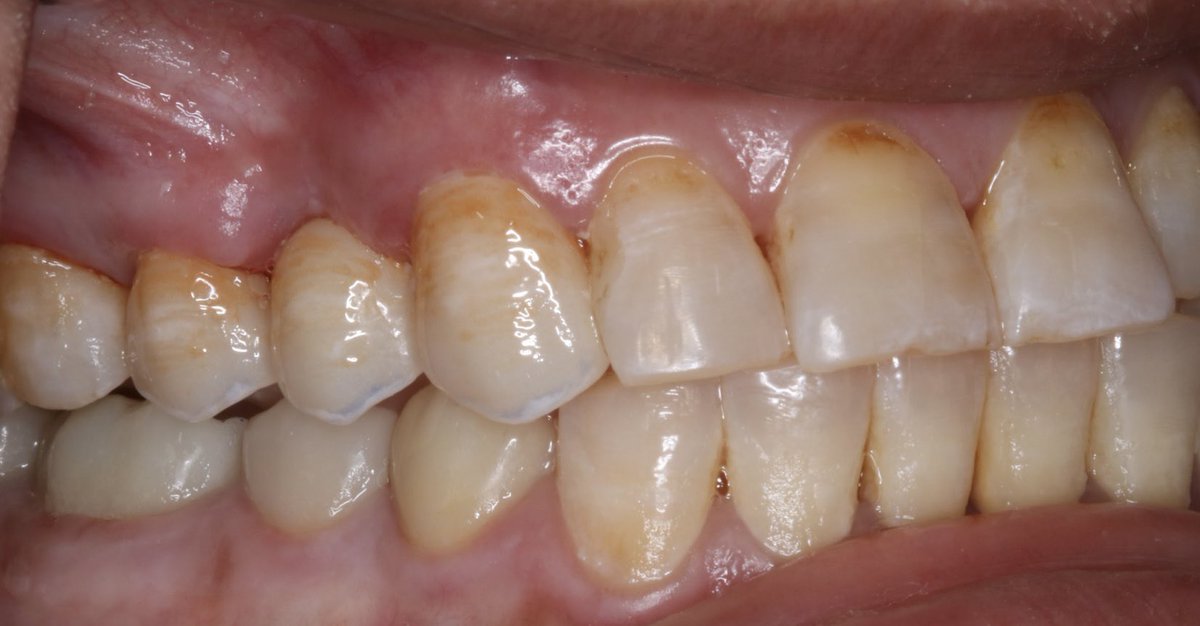

Zirconia crown on Endotreated #47 Implant supported crown on #46, The implant was placed by @alomar_ahmed